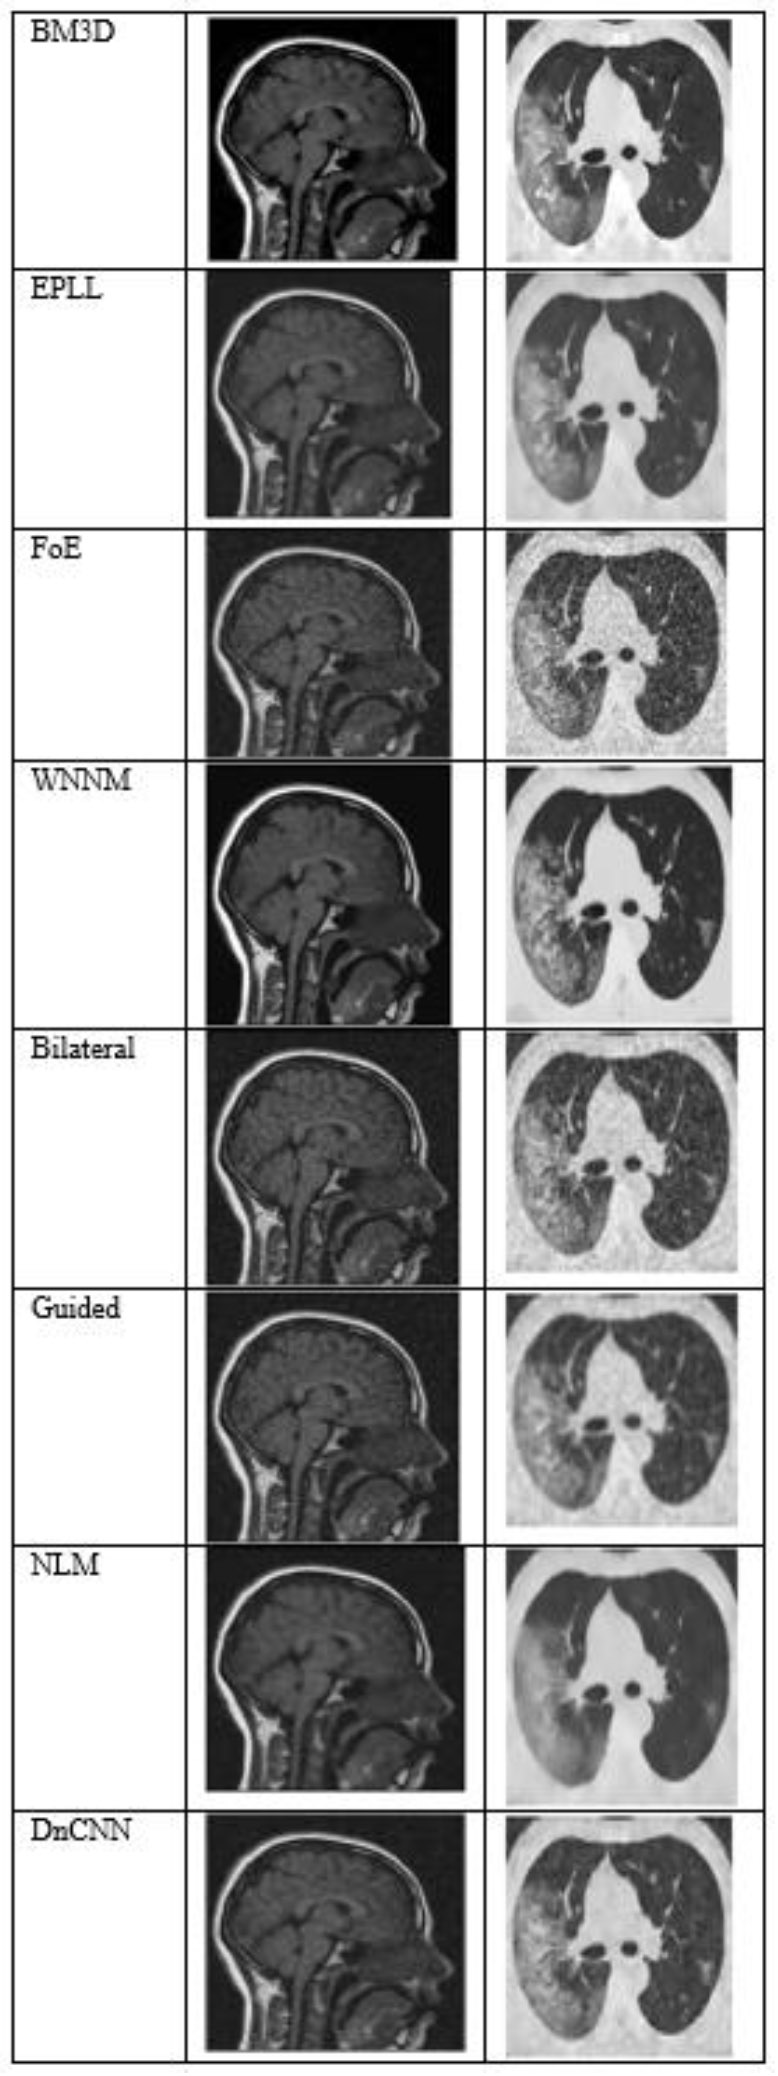

Fig. (7) shows the results at a noise variance of 0.5, where it has been observed that all the algorithms produce blurred images, except for the BM3D algorithm. However, the results of the BM3D algorithm are not so satisfactory. As a result, it has been observed that at a noise variance of 0.5, none of the algorithms performed well.

The output of different algorithms at Noise Variance 0.50.

All the algorithms performed poorly at the high-noise level (variance = 0.5), producing significantly distorted and degraded images. At this level of noise, even BM3D, which had demonstrated relative robustness, could not produce outputs appropriate for diagnosis. This result highlights the limitations of current denoising methods in high-noise or low-SNR conditions that are common in low-dose or accelerated medical imaging scenarios.